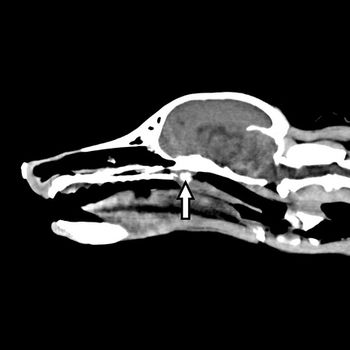

Dr. Clifford (Kip) Berry explains why radiographs are great for initially identifying the cause of vomiting in cats and dogs.

When a veterinary patient presents with sneezing and obstructive nasal breathing in your practice, how are you diagnosing the patient? Take the quiz to see if you're right.